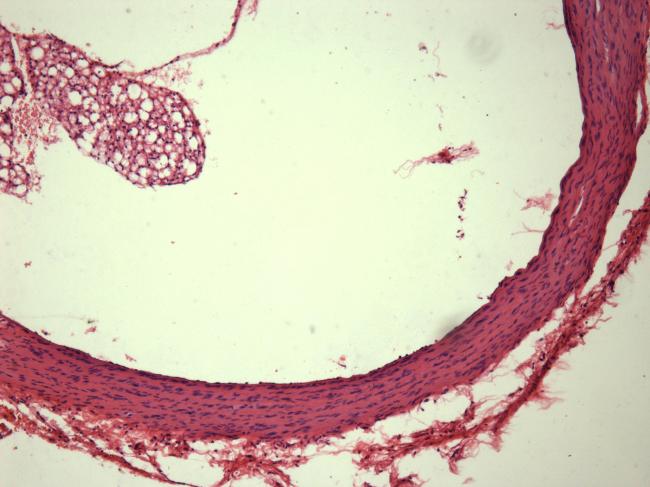

病理切片

| 各位老师们,有没有人作过大鼠心脏和肝脏的病理切片啊?能不能说一下每个步骤具体的时间啊,我发现脱水、透明的时间说法都不太一样,有没有做过的,怎么定时间效果比较好啊,谢谢了 |